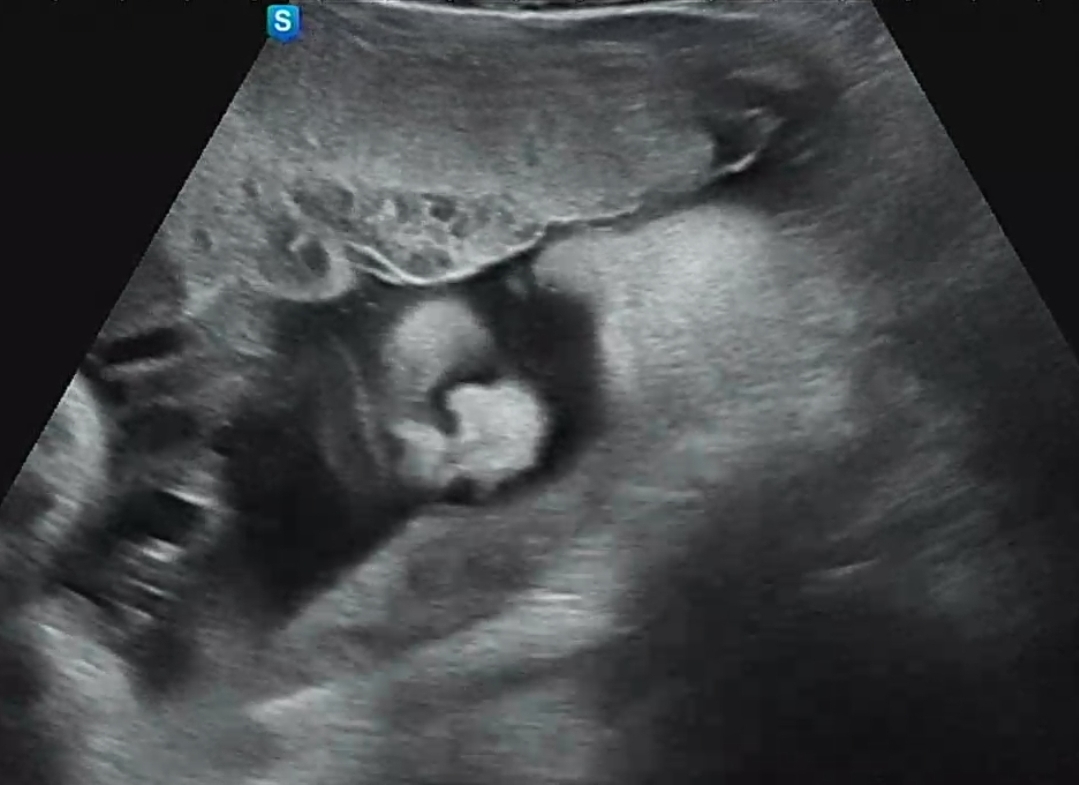

얼굴의 형태를 최대한 잘 나오게 잡아내다 보니 코가 뭉개져 보이지만, 그래도 포동포동 잘 크고 있어서 다행이다. 이 정도로 자라나고 있다면 출산 때 3kg 때를 기대해도 될 것 같다. 아내가 3kg 못 넘길까 봐 걱정하면서 마음을 많이 쓰는데, 추이를 봤을 때 3kg는 안전하게 넘길 수 있을 것 같다. 지금처럼만 잘 챙겨 먹고 잘 쉬고, 하면 된다고 격려해주었다.